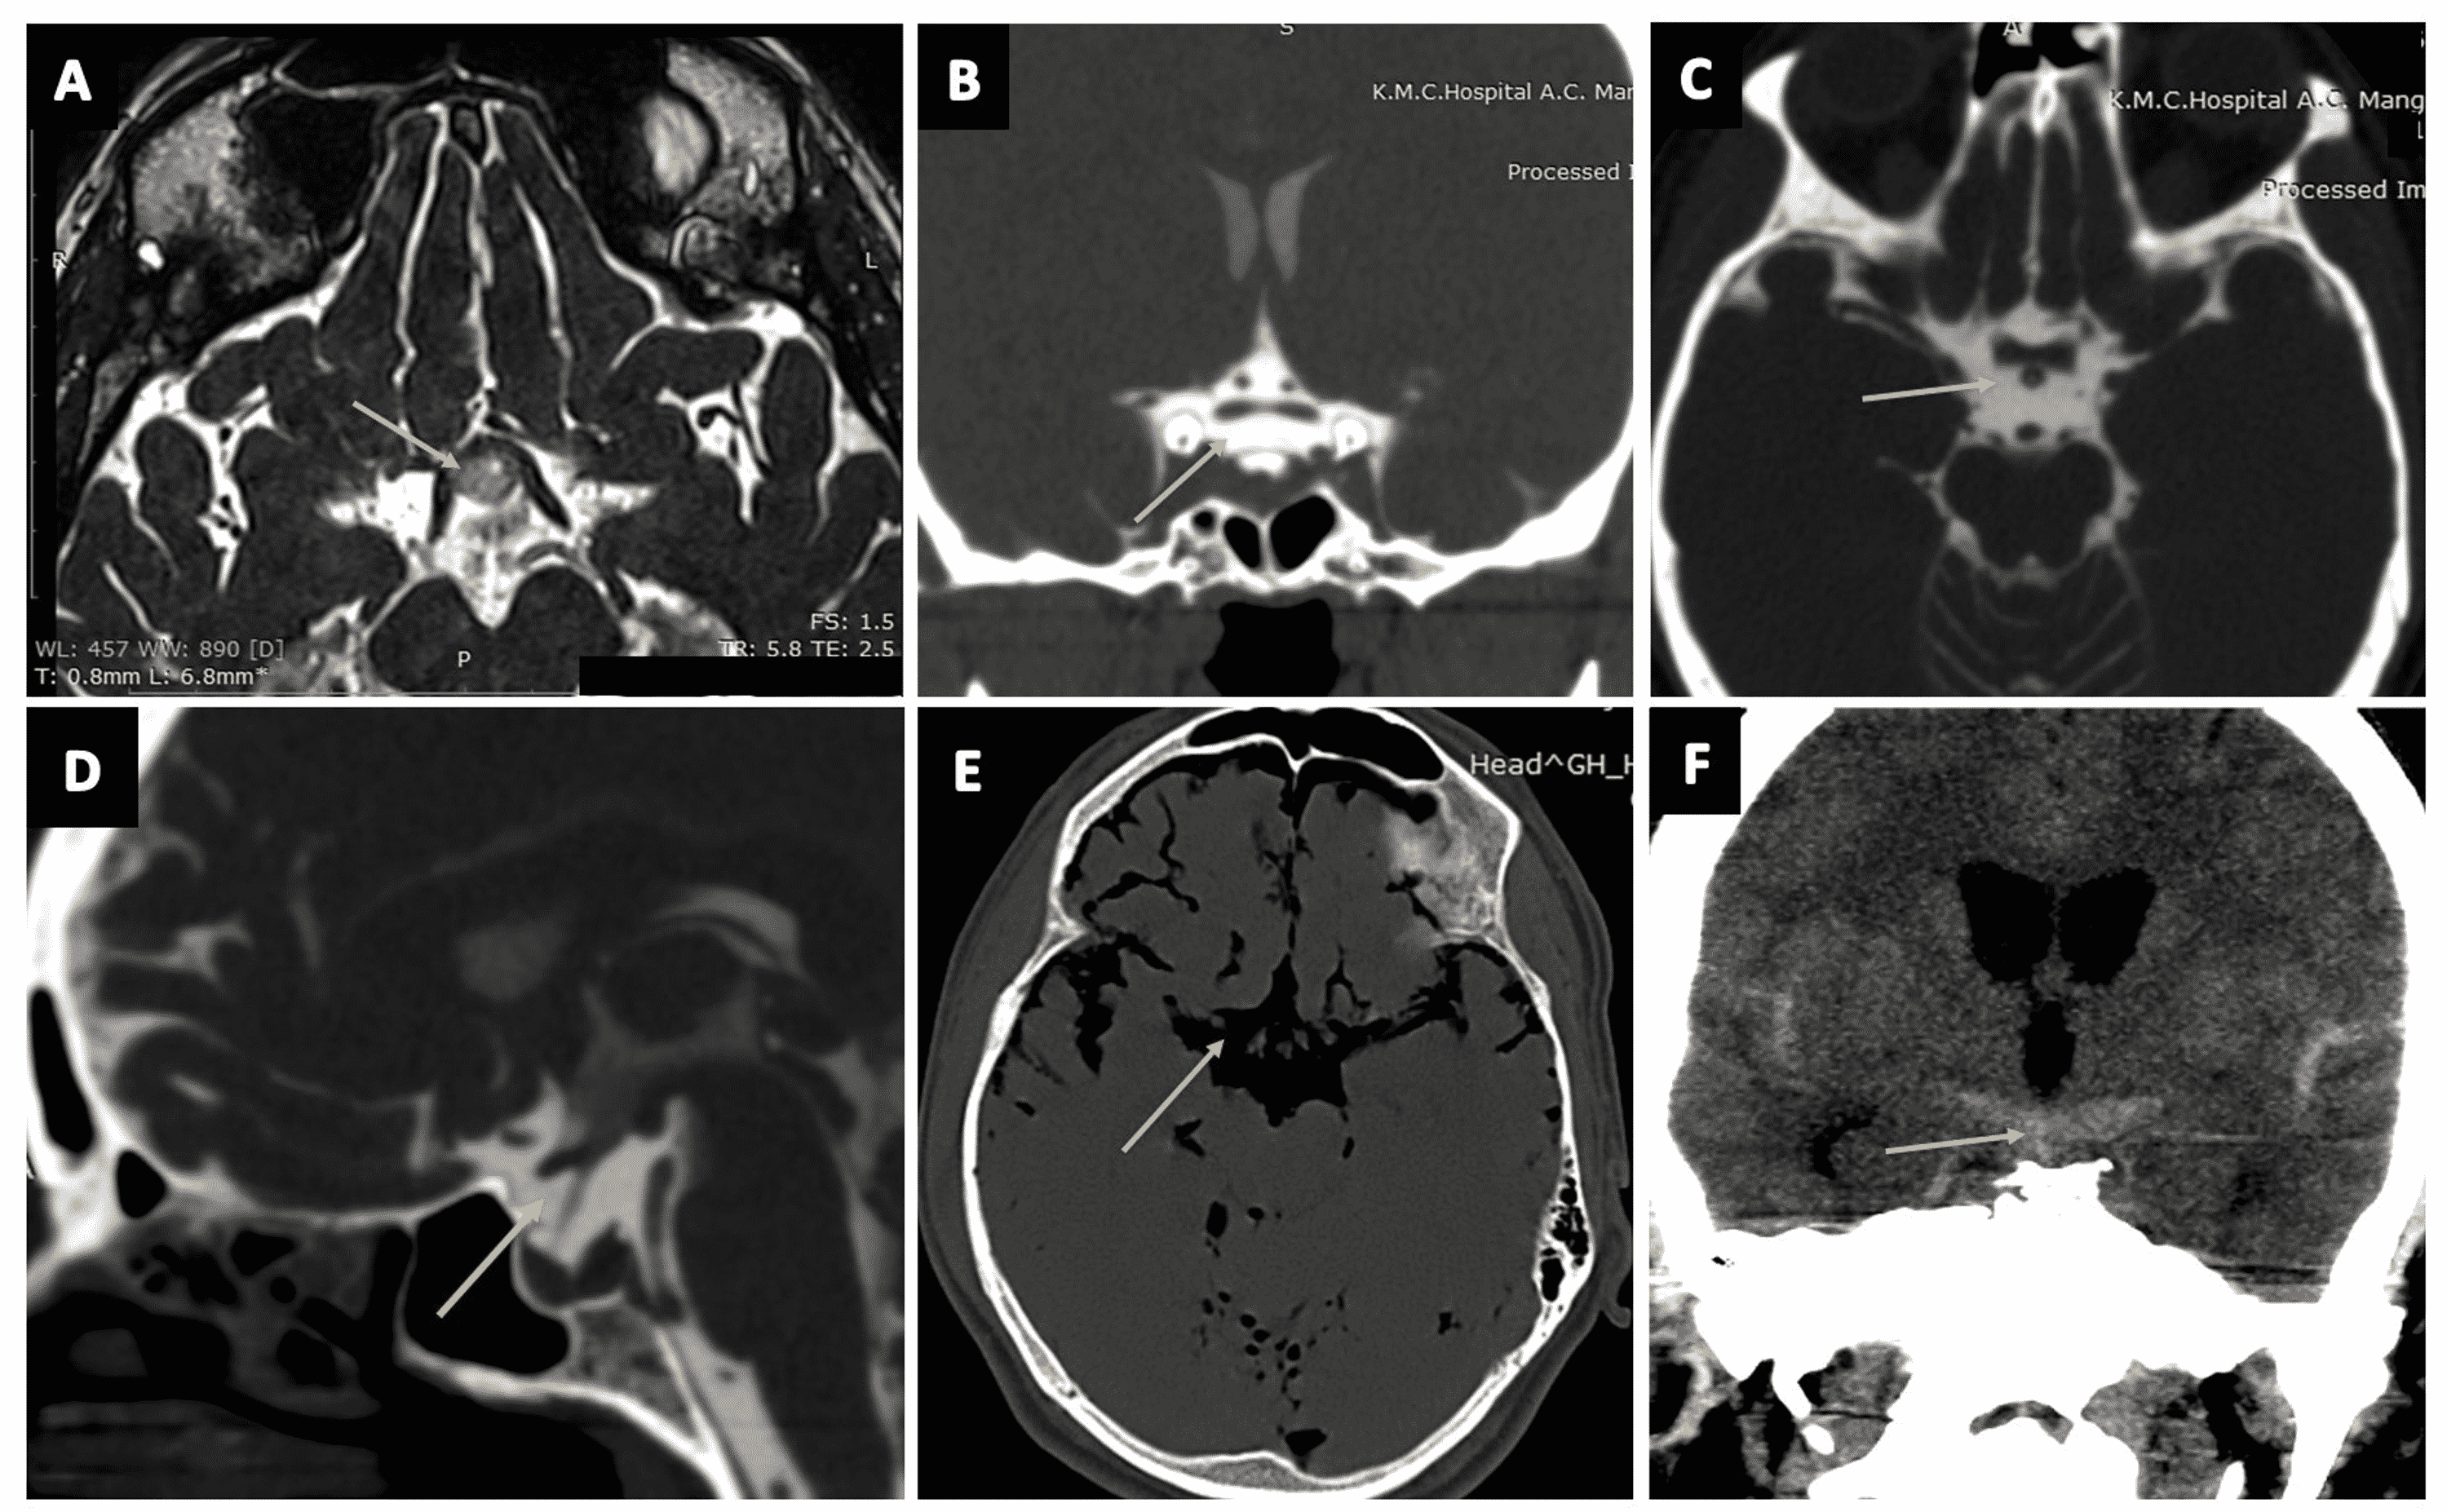

From www.cureus.com

Cureus Delineation of Subarachnoid Cisterns Using CT Cisternography, CT Brain Positive and Ct Anatomy Of Cisterns It is located between the splenium of the corpus callosum and the. It is located anterior to the third ventricle and contains the anterior cerebral arteries, the anterior. In this article we will discuss the anatomy, contents, function and clinical relevance of the subarachnoid cisterns. Learn this topic now at kenhub. Ambient and quadrigeminal cisterns or cistern of the great. Ct Anatomy Of Cisterns.